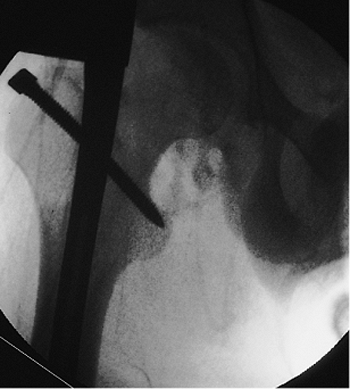

closed right-femur fracture as a result of a head-on motor vehicle

accident. The patient lost consciousness at the site of the accident

and experienced mild retrograde amnesia. On initial examination, the

physician found an obvious, closed, right, midshaft-femur deformity.

The peripheral pulses were intact, and the neurologic examination

showed no abnormalities. Cervical spine, chest, and pelvic radiographs

were normal. A cranial computed tomography (CT) scan was negative for

fracture or intracranial bleed. AP and lateral radiographs of the femur

showed a mid-diaphyseal transverse fracture (see Fig. 21.2). The patient

had an abdominal injury that required exploratory laparotomy. At

surgery, the patient was found to have a complete jejunal transection,

which was subsequently repaired. Immediately after the laparotomy, a

closed intramedullary nailing was performed with a static locked nail.

Because the fracture was mid-diaphyseal, a single distal screw was used

for fixation (Fig. 21.55).

The patient was mobilized on the second postoperative day. The fracture

healed uneventfully in 4 months with excellent restoration of function.

Figure 21.55. Postoperative radiograph.